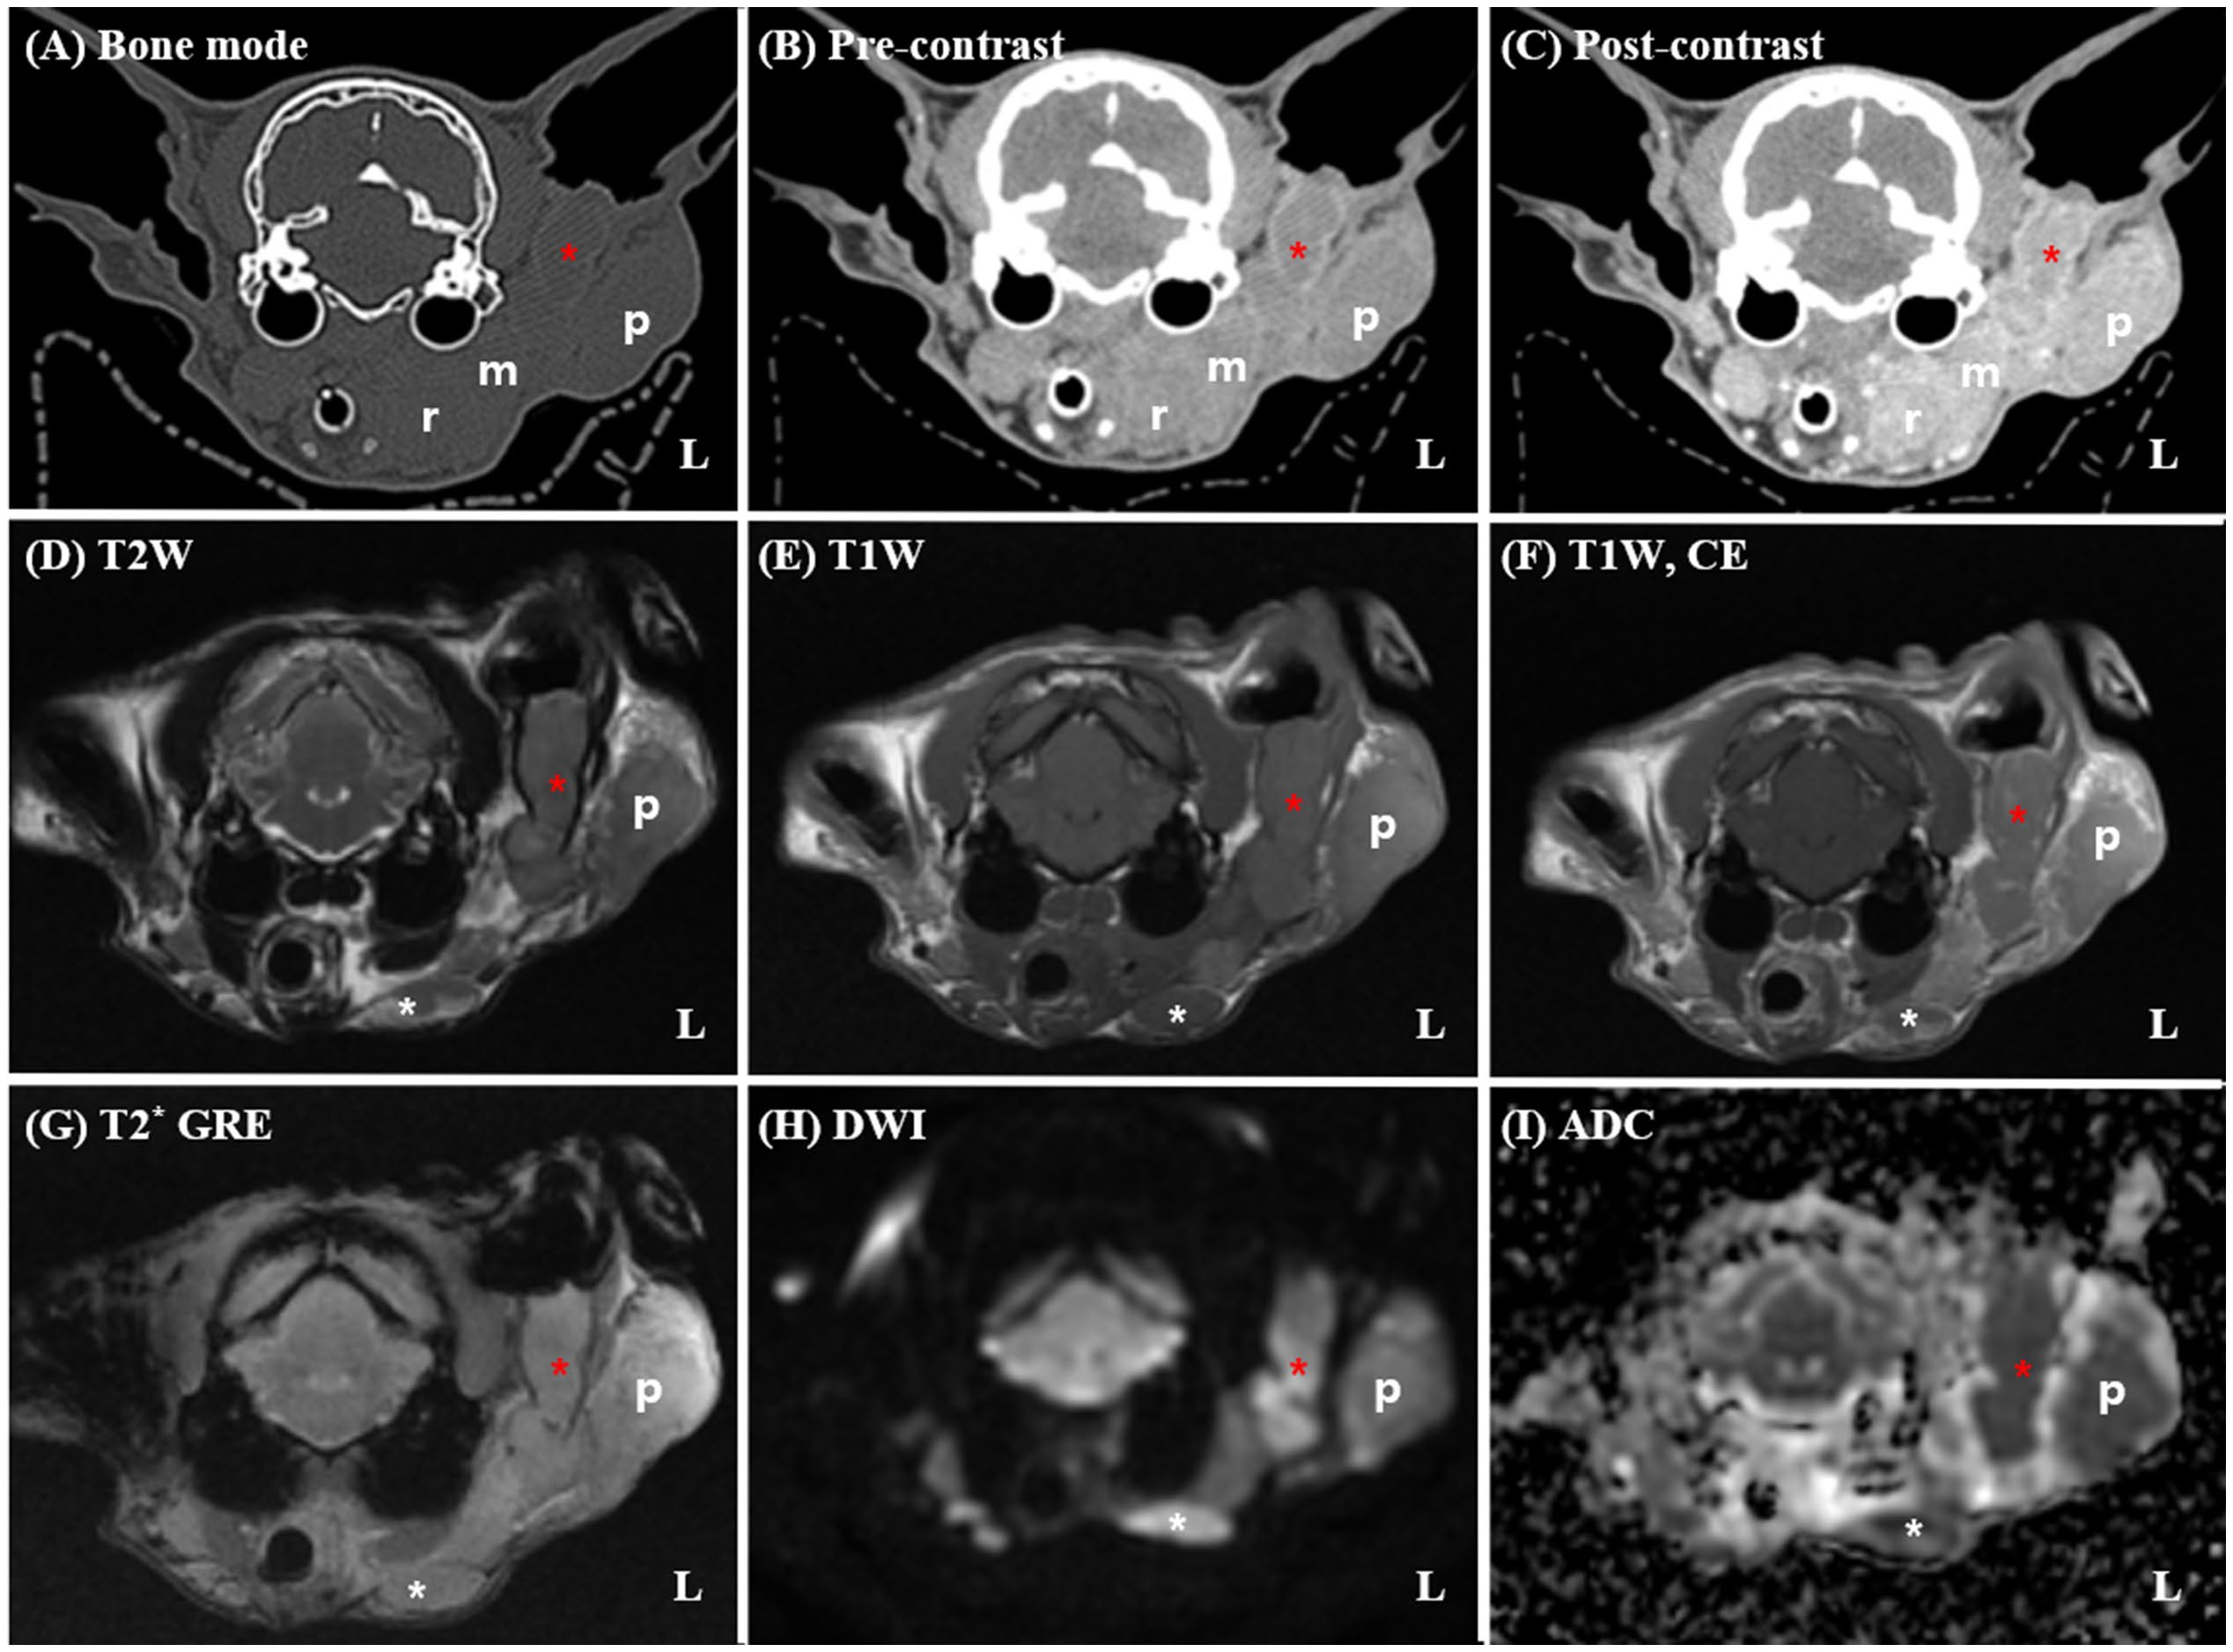

胸片未见肺转移;血液学及生化指标均在参考范围内。为评估肿瘤范围并制定放疗计划,全麻下行增强CT及MRI检查。CT显示左垂直耳道被巨大软组织肿物完全阻塞,并侵及邻近腮腺和下颌区域(图1)。增强扫描肿物呈显著均匀强化,左侧咀嚼肌及下颌腺亦呈相似强化且边界不清,提示肿瘤直接侵犯。

图1. 放疗前CT(A–C)与MRI(D–I)影像。CT及MRI示巨大软组织肿块(红色星号)占据左侧垂直外耳道,并延伸至邻近腮腺(p)及下颌区域。增强CT及T1加权MRI(C、F)显示肿块呈显著均匀强化,其与周围结构(咬肌及下颌腺,m)分界不清,提示直接侵犯。同侧下颌(白色星号)及内侧咽后淋巴结(r)明显增大。左侧外侧咽后淋巴结与主体肿块分界不清,疑肿瘤直接浸润;左侧肩前淋巴结及腮腺亦显著肿大(未示出)。未见骨质破坏或中耳受累。DWI(G)示肿块显著高信号,ADC图(H)对应低信号,提示弥散受限、细胞密度高。T1W:T1加权;T2W:T2加权;DWI:弥散加权;T1CE:增强T1加权;T2:T2加权;ADC:表观弥散系数。

MRI示肿物弥散明显受限(DWI高信号、ADC图低信号),平均ADC值397×10⁻⁶ mm²/s,提示细胞密度高。同侧多个淋巴结(下颌、内侧与外侧咽后、肩前)显著增大、均匀强化且弥散受限,疑为转移;右侧内侧咽后淋巴结轻度增大。未见肺转移、骨质破坏、鼓泡、鼻腔或脑实质异常。